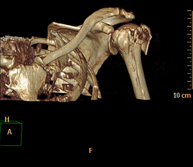

- TC Hombro

Exploración radiológica que mediante un sistema de rayos X y detectores que giran alrededor del paciente, reconstruyendo las imágenes por ordenador (TC Multidetector), permite el estudio de huesos, músculos y articulaciones del hombro.